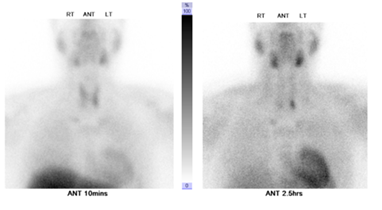

After five months from pancreatic surgery, Patient has been admitted electively after primary hyper parathyrodism localization imaging (Figure 4), to undergo total 4 glands parathyroidectomy and thymoctomy, with half parathyroid gland re implantation in the lower sternothyroid muscle, intraoperative PTH dropped from 236 to 15.5pg/ml, about 90% reduction, post procedure. It was without complication. Follow up Pathology report revealed4 glands hyperplasia.

Figure 4 NM parathyroid (with Sestamibi)

Figure 5 scintigraphic evidence suggestive of hyper functioning left lower parathyroid gland.